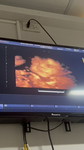

กำลังจะมีลูก

Vàngกำลังจะมีลูก